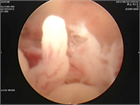

1. 関節水腫の原因となる疾患を、貯留した関節液の性状から、1)非炎症性2)炎症性3)化膿性4)血性の4グループから原因疾患を分類して考える(推奨度2)

1. その原因として、変性疾患、リウマチ性疾患、化膿性疾患、腫瘍性疾患、それに外傷などがある(推奨度2)